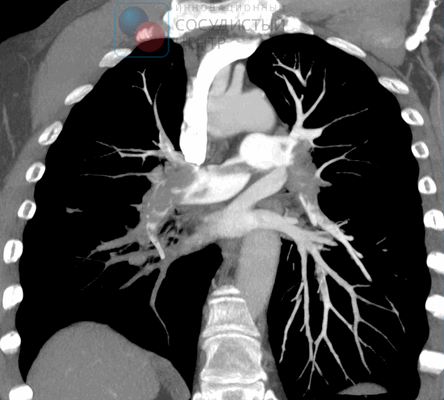

КТ-ангиография легочных артерий. Протяженный пристеночный тромб в просвете основного ствола левой легочной артерии

Мультиспиральная КТ с контрастированием сосудов позволяет визуализировать тромбы в лёгочной артерии, а также изменения лёгких, обусловленные другими заболеваниями, проявляющимися дефектами перфузии или наполнения. Чувствительность этого метода высока при локализации эмболов в крупных лёгочных артериях и существенно снижается при поражении субсегментарных и более мелких артерий.